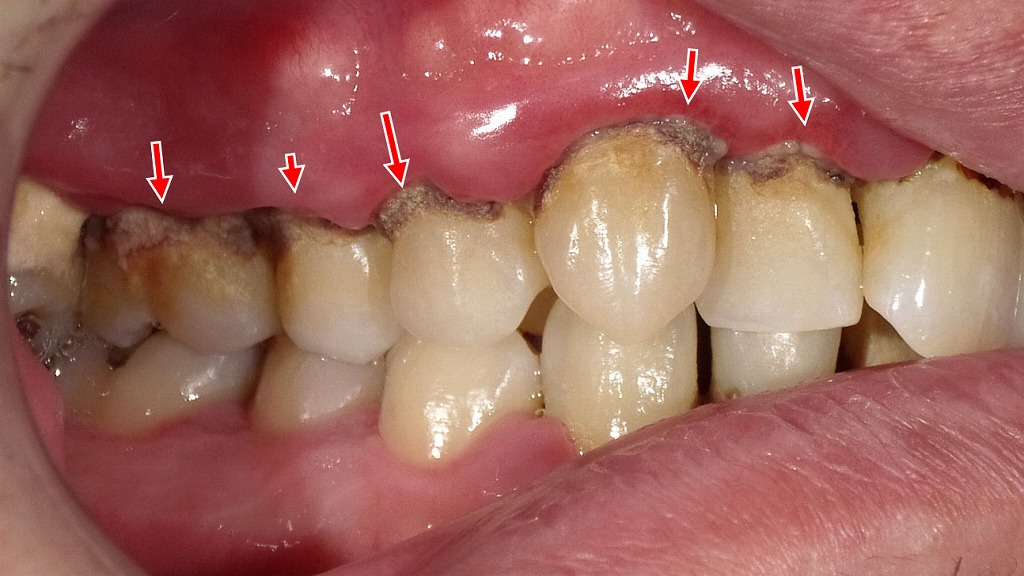

画像では、歯ぐきの腫れや発赤、歯の周囲に付着した歯石が認められ、進行した歯周病の状態です。

近年の研究では、歯周病菌が血流を介して全身に影響を及ぼし、アルツハイマー型認知症の発症や進行に関与する可能性が示唆されています。

歯周病による慢性的な炎症は、脳内の炎症反応を促進し、認知機能低下のリスクを高める要因の一つと考えられています。

お口の健康を守ることは、歯を残すだけでなく、将来の全身の健康や認知症予防にもつながる重要なケアです。